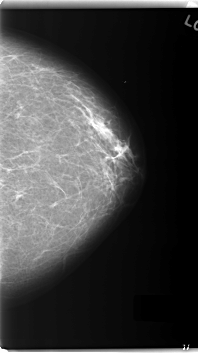

C_0163_1.LEFT_MLO

LEFT_MLO LINES 5968 PIXELS_PER_LINE 3464 BITS_PER_PIXEL 12 RESOLUTION 50 OVERLAY

FILE: C_0163_1.LEFT_MLO.OVERLAY

TOTAL_ABNORMALITIES 1

ABNORMALITY 1

LESION_TYPE MASS SHAPE OVAL MARGINS MICROLOBULATED

ASSESSMENT 5

SUBTLETY 5

PATHOLOGY MALIGNANT

TOTAL_OUTLINES 1